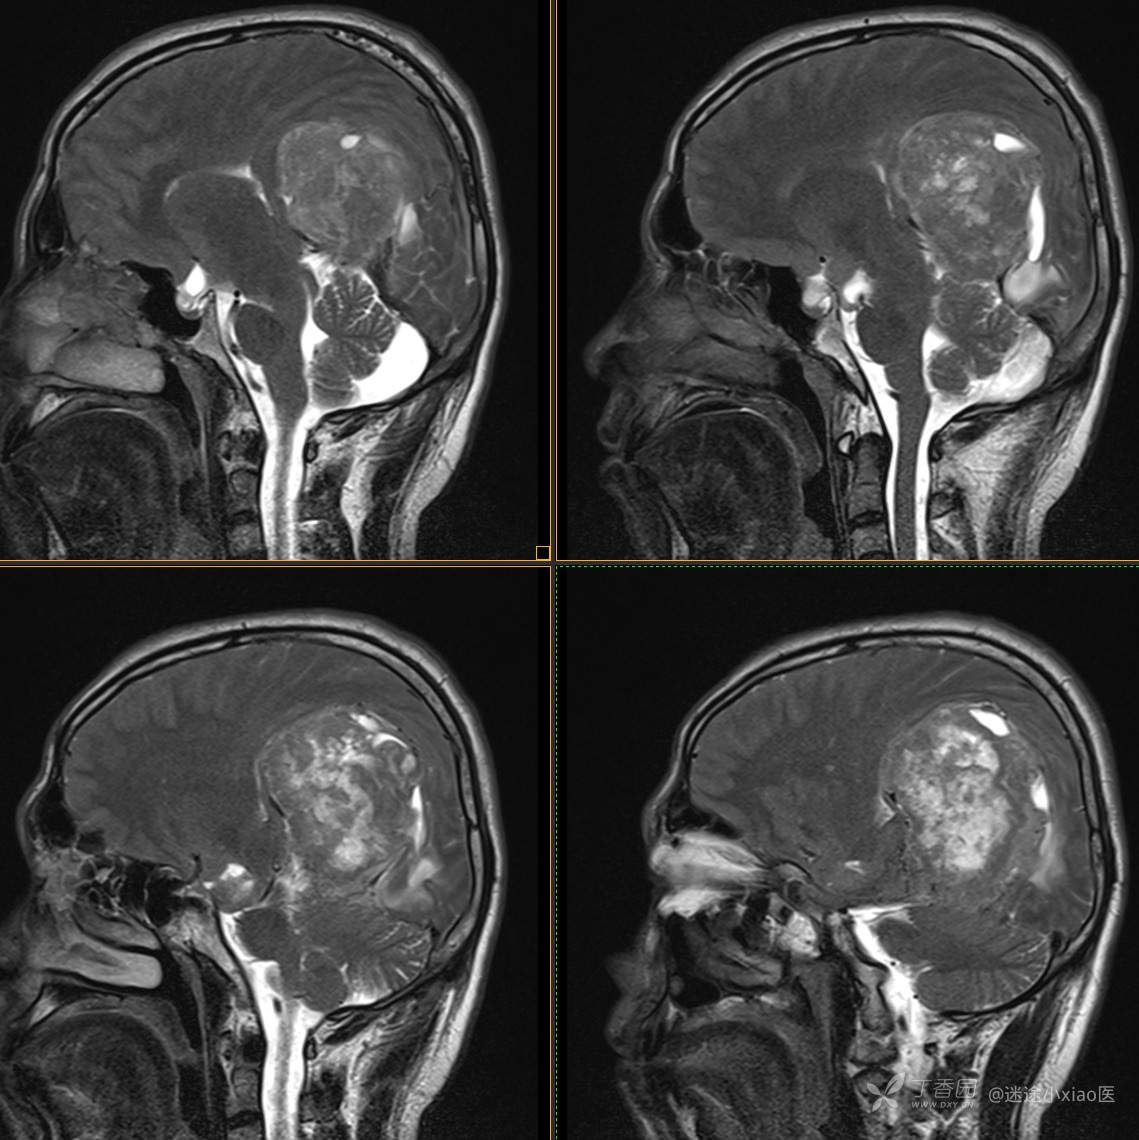

患者年龄:43

患者性别:男

简要病史:头痛3月余,查体无殊